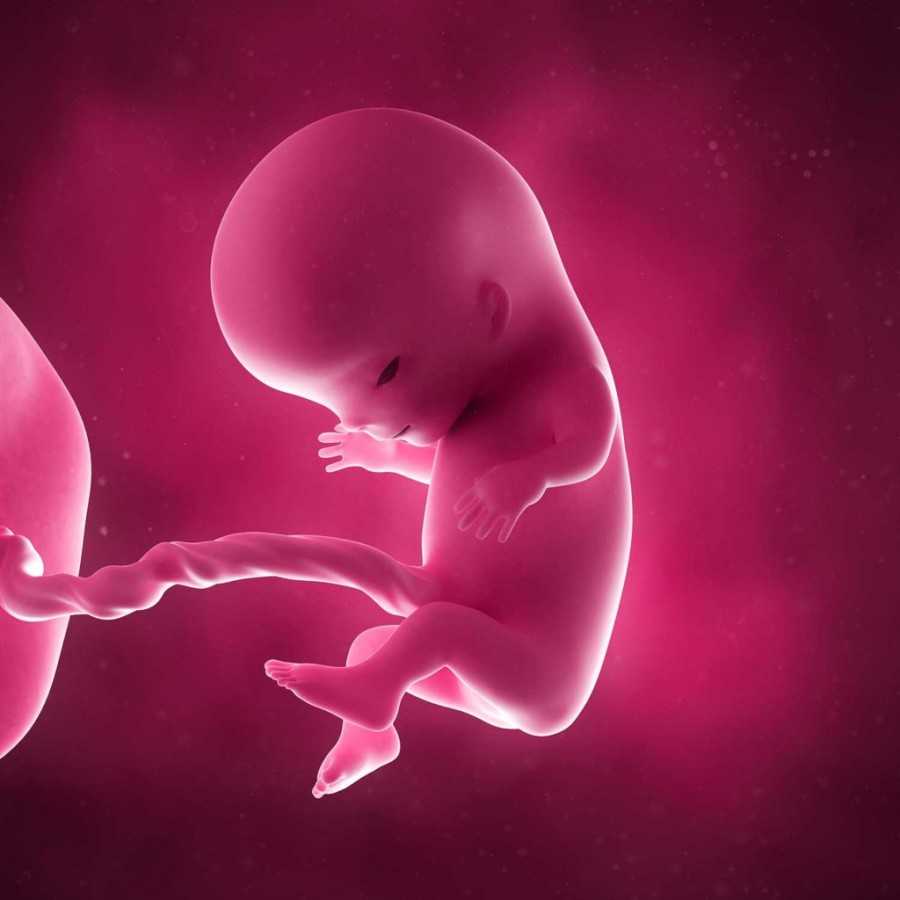

Вот так выглядит твой малыш на 9 неделе (фото плода)

Конечно, больше всего будущим родителям интересно знать, что происходит с малышом на 8–9 неделе. Он растет, и к этому сроку беременности длина плода уже достигает 2,5 см. Это примерно небольшая виноградинка или вишенка. Он свободно расположен в полости матки. При этом вес его составляет 4 грамма. Но, несмотря на небольшие размеры, при проведении ультразвукового исследования, у малыша уже можно различить личико и половой бугорок.

Также на врач может увидеть и сообщить родителям много другой полезной информации, а также показать плод на мониторе, присоединенном к датчику УЗИ. Эмбрион на 9 неделе жизни выглядит как человек, явно различимы голова, лицо с носиком и губами, ушные раковины, тельце, ручки и ножки с маленькими пальчиками. Но у ребенка все есть небольшой хвостик, а пропорции тела далеки от пропорций взрослого человека, и даже новорожденного. Голова эмбриона гораздо больше и доминирует над телом.

Как выглядит эмбрион на 9 неделе? Ваш кроха еще подрос. У него уже начинает формироваться личико, удлиняются конечности, появляются пальчики. Именно на данном этапе ребенок прогрессирует и становится не эмбрионом, а плодом, поскольку большой палец на руке разворачивается так, что прижимается к ладони с внутренней стороны (противостоящий палец).

Уже можно заметить пуповину. И именно с этой недели ваш малыш начинает развиваться быстрее вдвое.